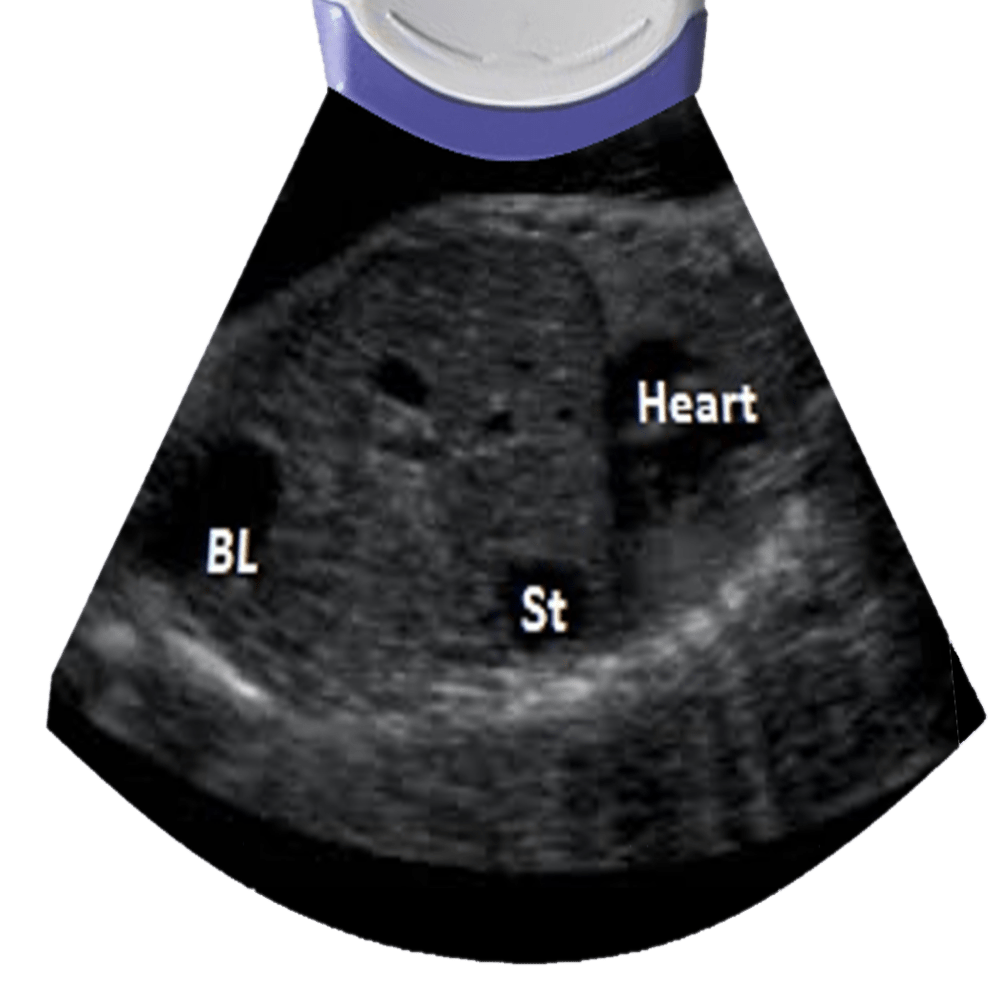

SECOND TRIMESTER ULTRASOUND WITH PICTURES MADE EASY FOR STUDENTS YouTube X Ray In Pregnancy Second Trimester In the first two weeks of. Even though the fetus is more resistant to the radiation during the second and third trimester, a high dose of radiation (greater. Timely investigation and management of complex medical symptoms in pregnancy is essential to reduce maternal. The use of other imaging modalities—such as plain radiography, computed tomography (ct), and magnetic resonance imaging (mri)—in. X Ray In Pregnancy Second Trimester.

OB Ultrasound Second Trimester (The Basics) Sonographic Tendencies X Ray In Pregnancy Second Trimester 1 imaging plays an important role in the investigation of many conditions in pregnancy, but also has potential to cause harm. The most common indications for acute ct during pregnancy are : The use of other imaging modalities—such as plain radiography, computed tomography (ct), and magnetic resonance imaging (mri)—in pregnancy is increasing. Even though the fetus is more resistant to. X Ray In Pregnancy Second Trimester.